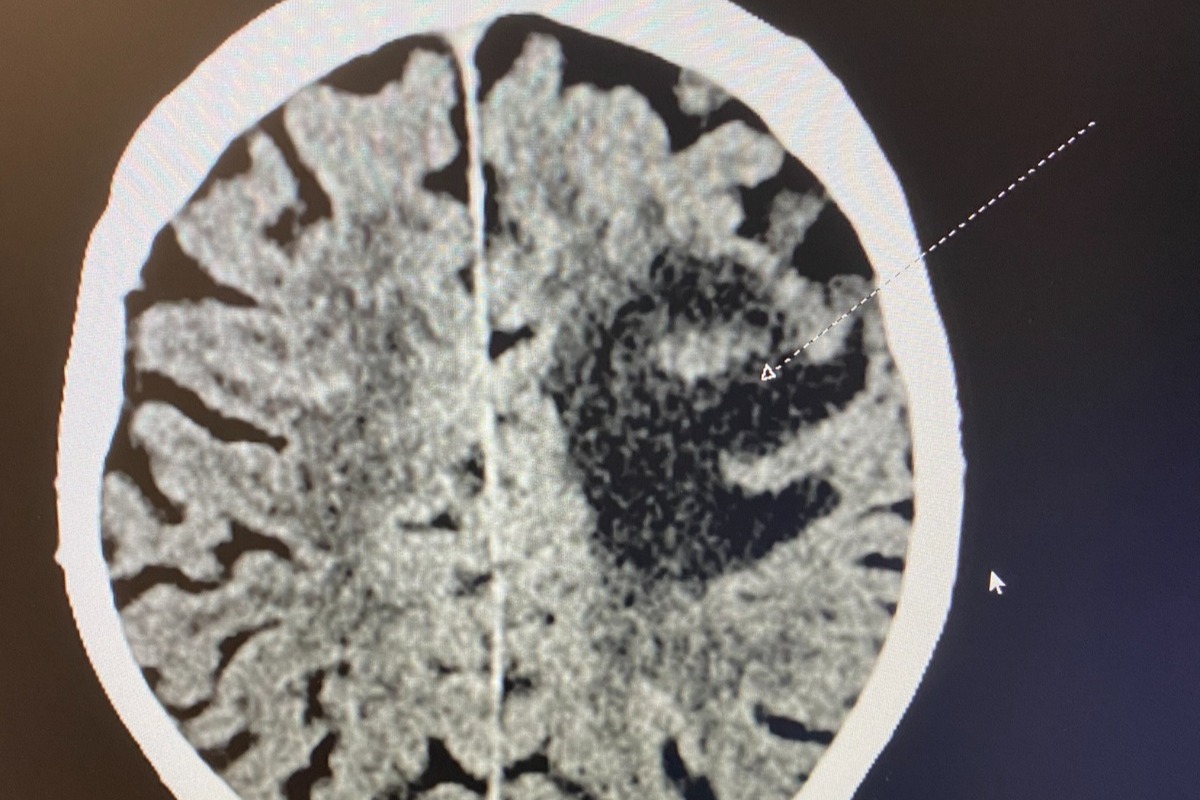

The diagnostic CT scan of one of the larger tumors on Dad's brain.

The diagnostic CT scan of one of the larger tumors on Dad's brain.In the blink of an eye, my father had gone from having many years ahead of him to a terminal diagnosis with possibly a year to live with treatment. With the help of my sister, we have since brought him back to Bend, where he lives with my husband and I in our one-bedroom apartment so that we can care for him full time as he undergoes aggressive treatment that takes a massive toll on him.